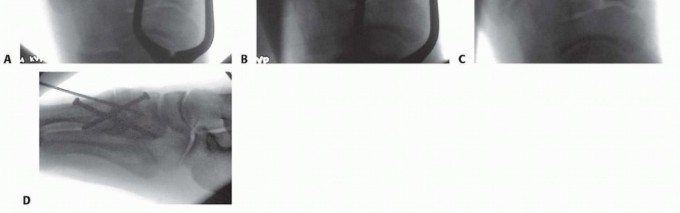

Initial radiographic evaluation consists of non-weight-bearing anteroposterior (AP), oblique, and lateral views of the foot, which, depending on the extent of intra-articular displacement, may provide sufficient diagnostic information (

FIG 3A-C

).

Fluoroscopic stress views may be helpful in more subtle injuries; however, these studies are painful and generally require anesthesia.

We therefore prefer weight-bearing radiographs of the foot for more subtle injuries (

FIG 3D-H

); comparison weight-bearing radiographs of the contralateral foot may also be obtained where necessary.

The weight-bearing AP view of the foot will demonstrate intra-articular displacement through the first and second tarsometatarsal joints (so-called Lisfranc joint), intercuneiform joint, and naviculocuneiform joint; fractures through the first and second metatarsal bases, medial and middle cuneiforms, and proximal extension into the navicular; and the extent of columnar shortening or asymmetry.

The medial border of the second metatarsal should align with the medial border of the middle cuneiform (

FIG 3D

The oblique view will reveal intra-articular displacement through the third, fourth, and fifth tarsometatarsal joints and fractures of the third, fourth, and fifth metatarsal bases, lateral cuneiform, and cuboid.

The medial borders of the third and fourth metatarsals should align with the medial borders of the lateral cuneiform and cuboid, respectively (

FIG 3E

The lateral view may reveal dorsal-plantar displacement of fractures or dislocations as well as any flattening of the medial longitudinal arch, thereby reflecting the status of the weight-bearing medial column and first ray (

FIG 3F

FIG 3

• Non-weight-bearing AP (

A

), oblique (

B

), and lateral (

C

) radiographs of grossly unstable, purely ligamentous, Lisfranc dislocation involving all five tarsometatarsal articulations. Marked lateral subluxation through all five tarsometatarsal joints is evident on the AP and oblique views, and significant dorsal displacement is evident on the lateral view. Weight-bearing lateral (

D

), AP (

E

), and oblique (

F

), and non-weight-bearing (

G

) and oblique (

H

) radiographs of more subtle Lisfranc injury. Lateral and plantar subluxation (

black arrows

) is evident on the weight-bearing radiographs, and displacement of normal radiographic landmarks (

black lines

) confirms injury.